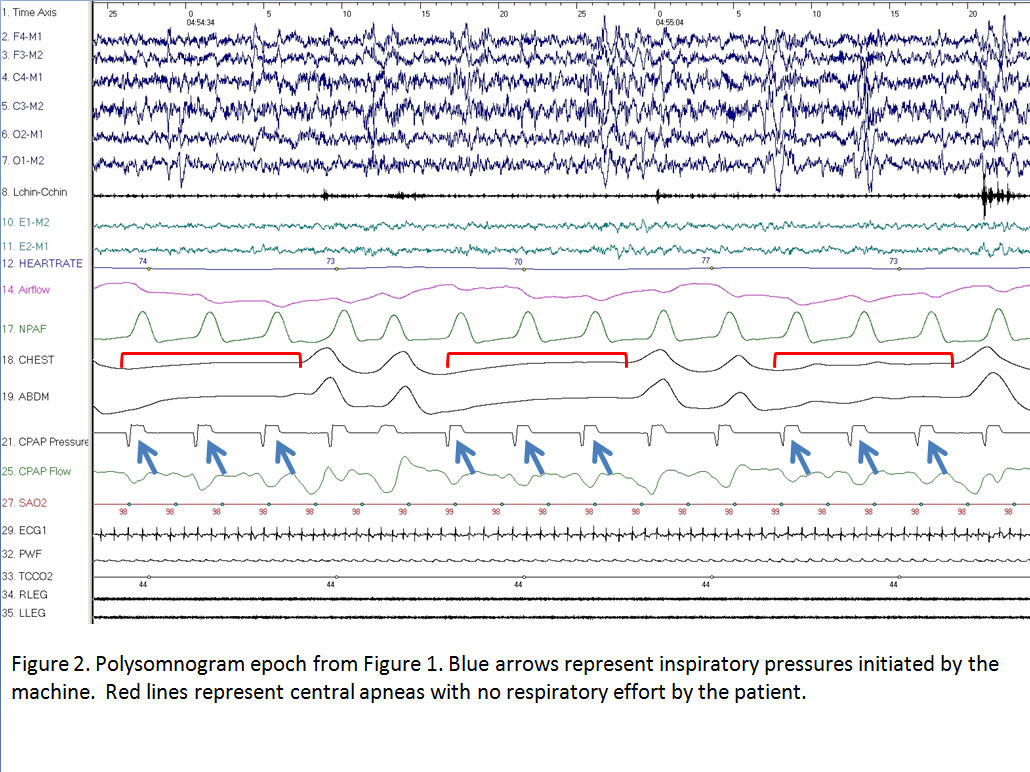

1. The breaths are adequately initiated by the ventilator but because of a short inspiratory time (Ti) the breaths are cycled off before there is time for the delivered pressures to move the chest wall, resulting in central apneas (figure 2).

During this titration study the patient was switched from ST to PC mode with a set respiratory rate and Ti. In this situation the machine initiates and delivers breaths at a set pressure and rate. Any additional spontaneous breaths taken by the patient, between the machine initiated breaths, are not supported by pressure from the machine. In PC mode, the ventilator cycles off the breaths when the pressure is delivered for a set Ti. In this sample, the Ti was set at 0.3 seconds which is extremely short for the patient’s own respiratory rate of 12bpm. For a normal inspiratory:expiratory ratio of 1:2, this respiratory rate should allow inspiratory time of 1.66 seconds (vs 0.3 seconds) and an exhalation time of 3.34 seconds. The short Ti in this case could not sustain the delivered breaths for long enough to move the chest wall with resulting central apneas (Figure 2, red lines). The blue arrows in figure 2 clearly represent breaths initiated by the ventilator and not the patient as there is no evidence of respiratory effort to initiate the breaths in either the chest or abdominal leads on the patient.